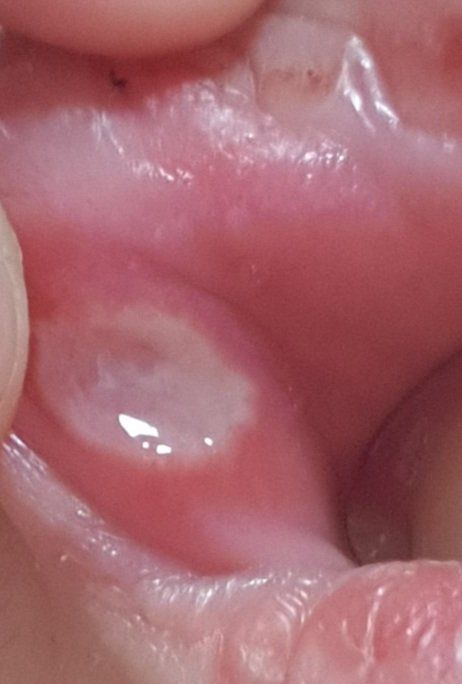

지금 2주정도 사진과 같은 상태입니다

- 생긴지 2주되었다고 한다면 처음보다 크기나 통증이 커졌는지 줄어들었는지는 질문하신 분께서 가장 잘 아실 것 같습니다. 제가 느끼기엔 지금도 크기가 꽤 커보입니다. 보통 2주정도면 어느정도 호전이 되는데, 전 후 사진이 없어서 정확히는 판단하기 어렵습니다.

말씀해주신 것은 아프타성 구내염의 가능성이 있어 보입니다.